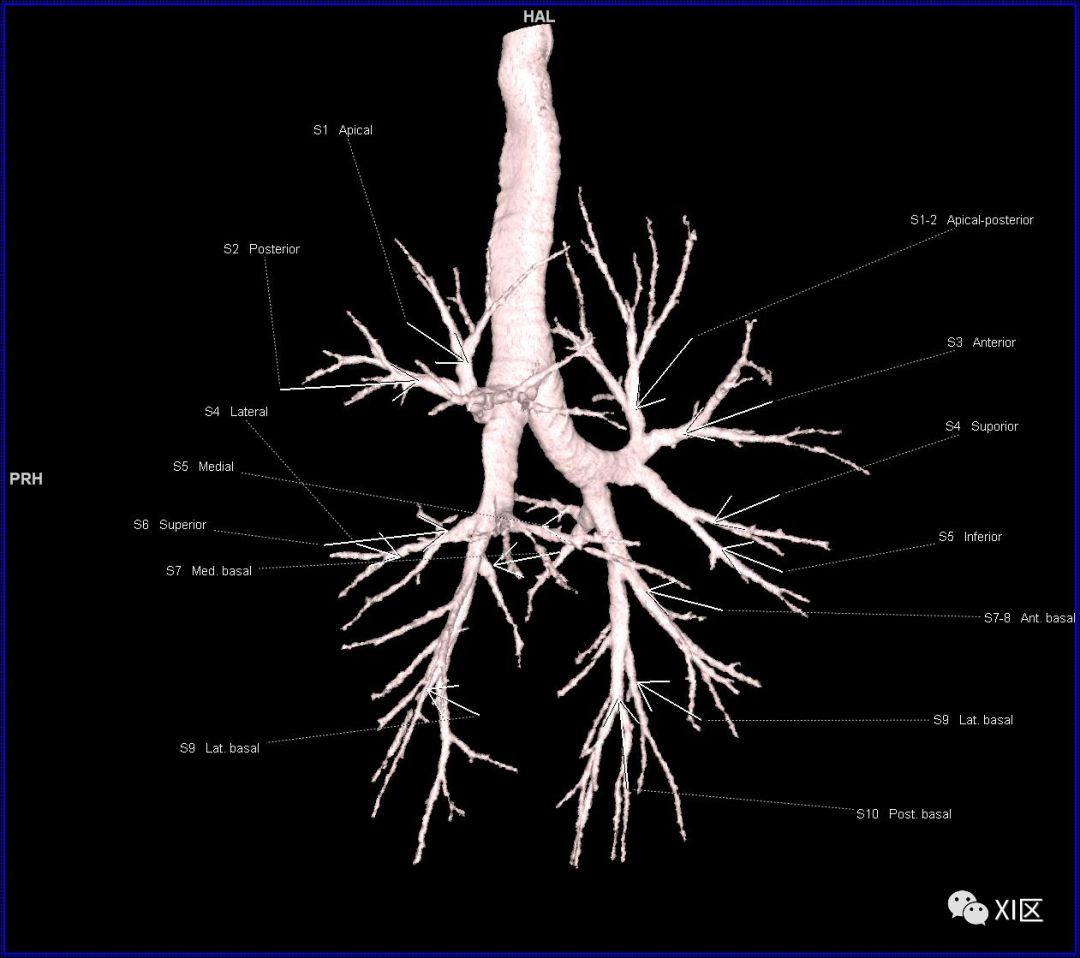

段支气管的命名

段支气管的命名(图片源自网络)

人的支气管(第1级)至肺泡约有24级分支。支气管经肺门入肺,分为叶支气管(第2级),右肺3支,左肺2支。叶支气管分为段支气管(第3~4级),左肺8支、右肺10支。段支气管就是肺的分段的依据。段支气管反复分支为小支气管(第5~10级),继而再分支为细支气管(第11~13级),细支气管又分支为终末细支气管(第14~16级)。从叶支气管至终末细支气管为肺内的导气部。终末细支气管以下的分支为肺的呼吸部,包括呼吸细支气管(第17~19级)、肺泡管(第20~22级)、肺泡囊(第23级)和肺泡(第24级)。

在进行肺的分段时,可以上下观察浏览,沿着相应气管的走形可以更容易准确地进行分段。